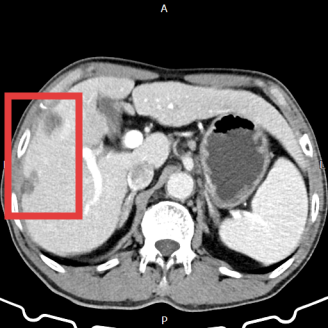

此前,雷先生因无明显诱因右上腹胀痛不适入院,经上腹部磁共振检查发现肝占位性病变。鉴于病灶的位置与特性,如何在不加重肝脏负担,尽可能保留正常肝组织的前提下彻底处理病灶,成为治疗的关键与难点。

肝右叶肿瘤

肿瘤微波消融术后